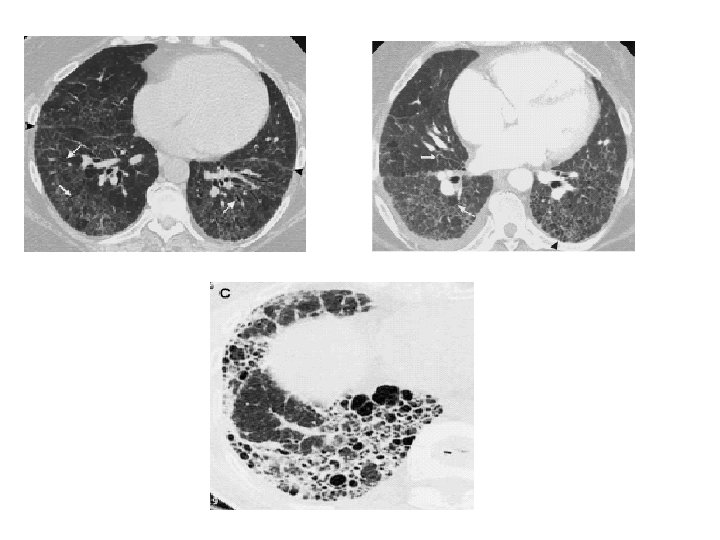

HRCT features of UIP/IPF • Basal/peripheral predominance • Reticular lines • Traction bronchiectasis • Honeycombing • ± Ground glass

CT features not suggestive of UIP